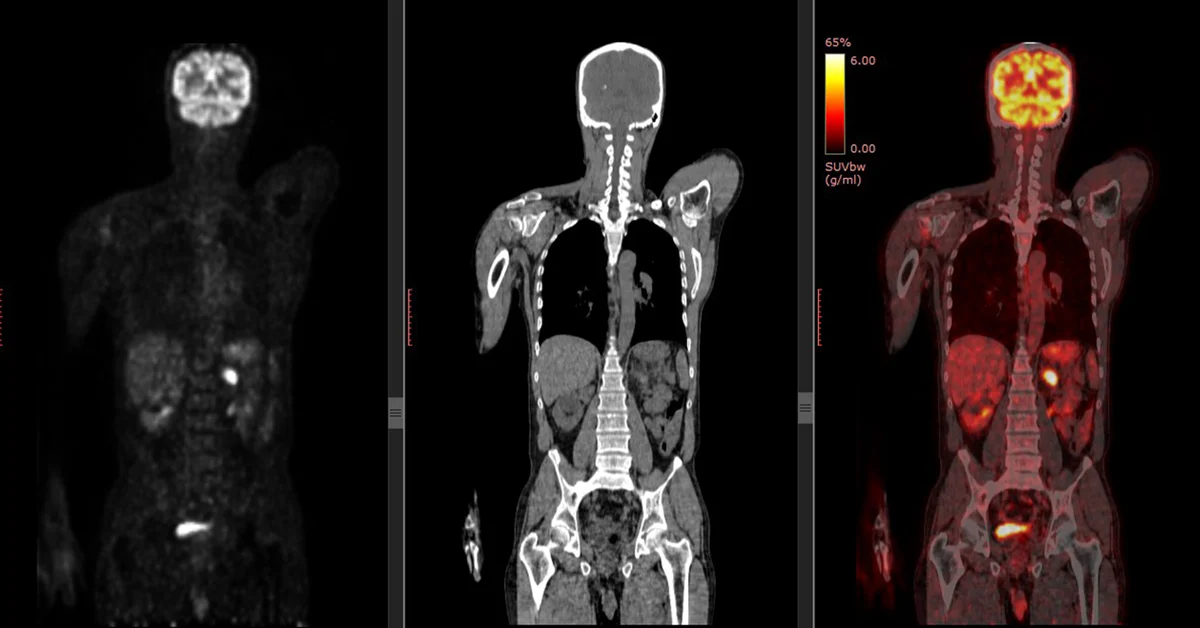

Why do we like to use FDG as a pharmaceutical in PET?

It’s a sugar that is very similar to glucose

As cancer uses metabolic processes, it uses glucose as its main form of energy – we take advantage of this by binding the radioactive material with a pharmaceutical that’s similar in structure to glucose so that we can visualize where the cancer is based on its metabolism

What happens to the FDG when it’s up-taken by the cancer cells?

Instead of breaking down FDG and using it as energy, it will just accumulate in the cancer cell – makes the cancer more visible on our PET images

Why do we ask the patient to fast before we inject?

If the patient were to eat, food that contains glucose or carbohydrates will cause F-18 FDG to compete for uptake in the body

Need a proper level of blood sugar – if too high, there will be competition between the F-18 FDG with the glucose already present in the body

What is the ideal blood glucose level and why?

Ideally we want a blood glucose level less than 120 mg/dL as it allows for better uptake of FDG – not as much competition for the tracer with the glucose already present in the body

What is the ideal condition that we want the patient to be in regarding their blood glucose levels?

Want the patient to be hypoglycemic – why we ask them to fast!